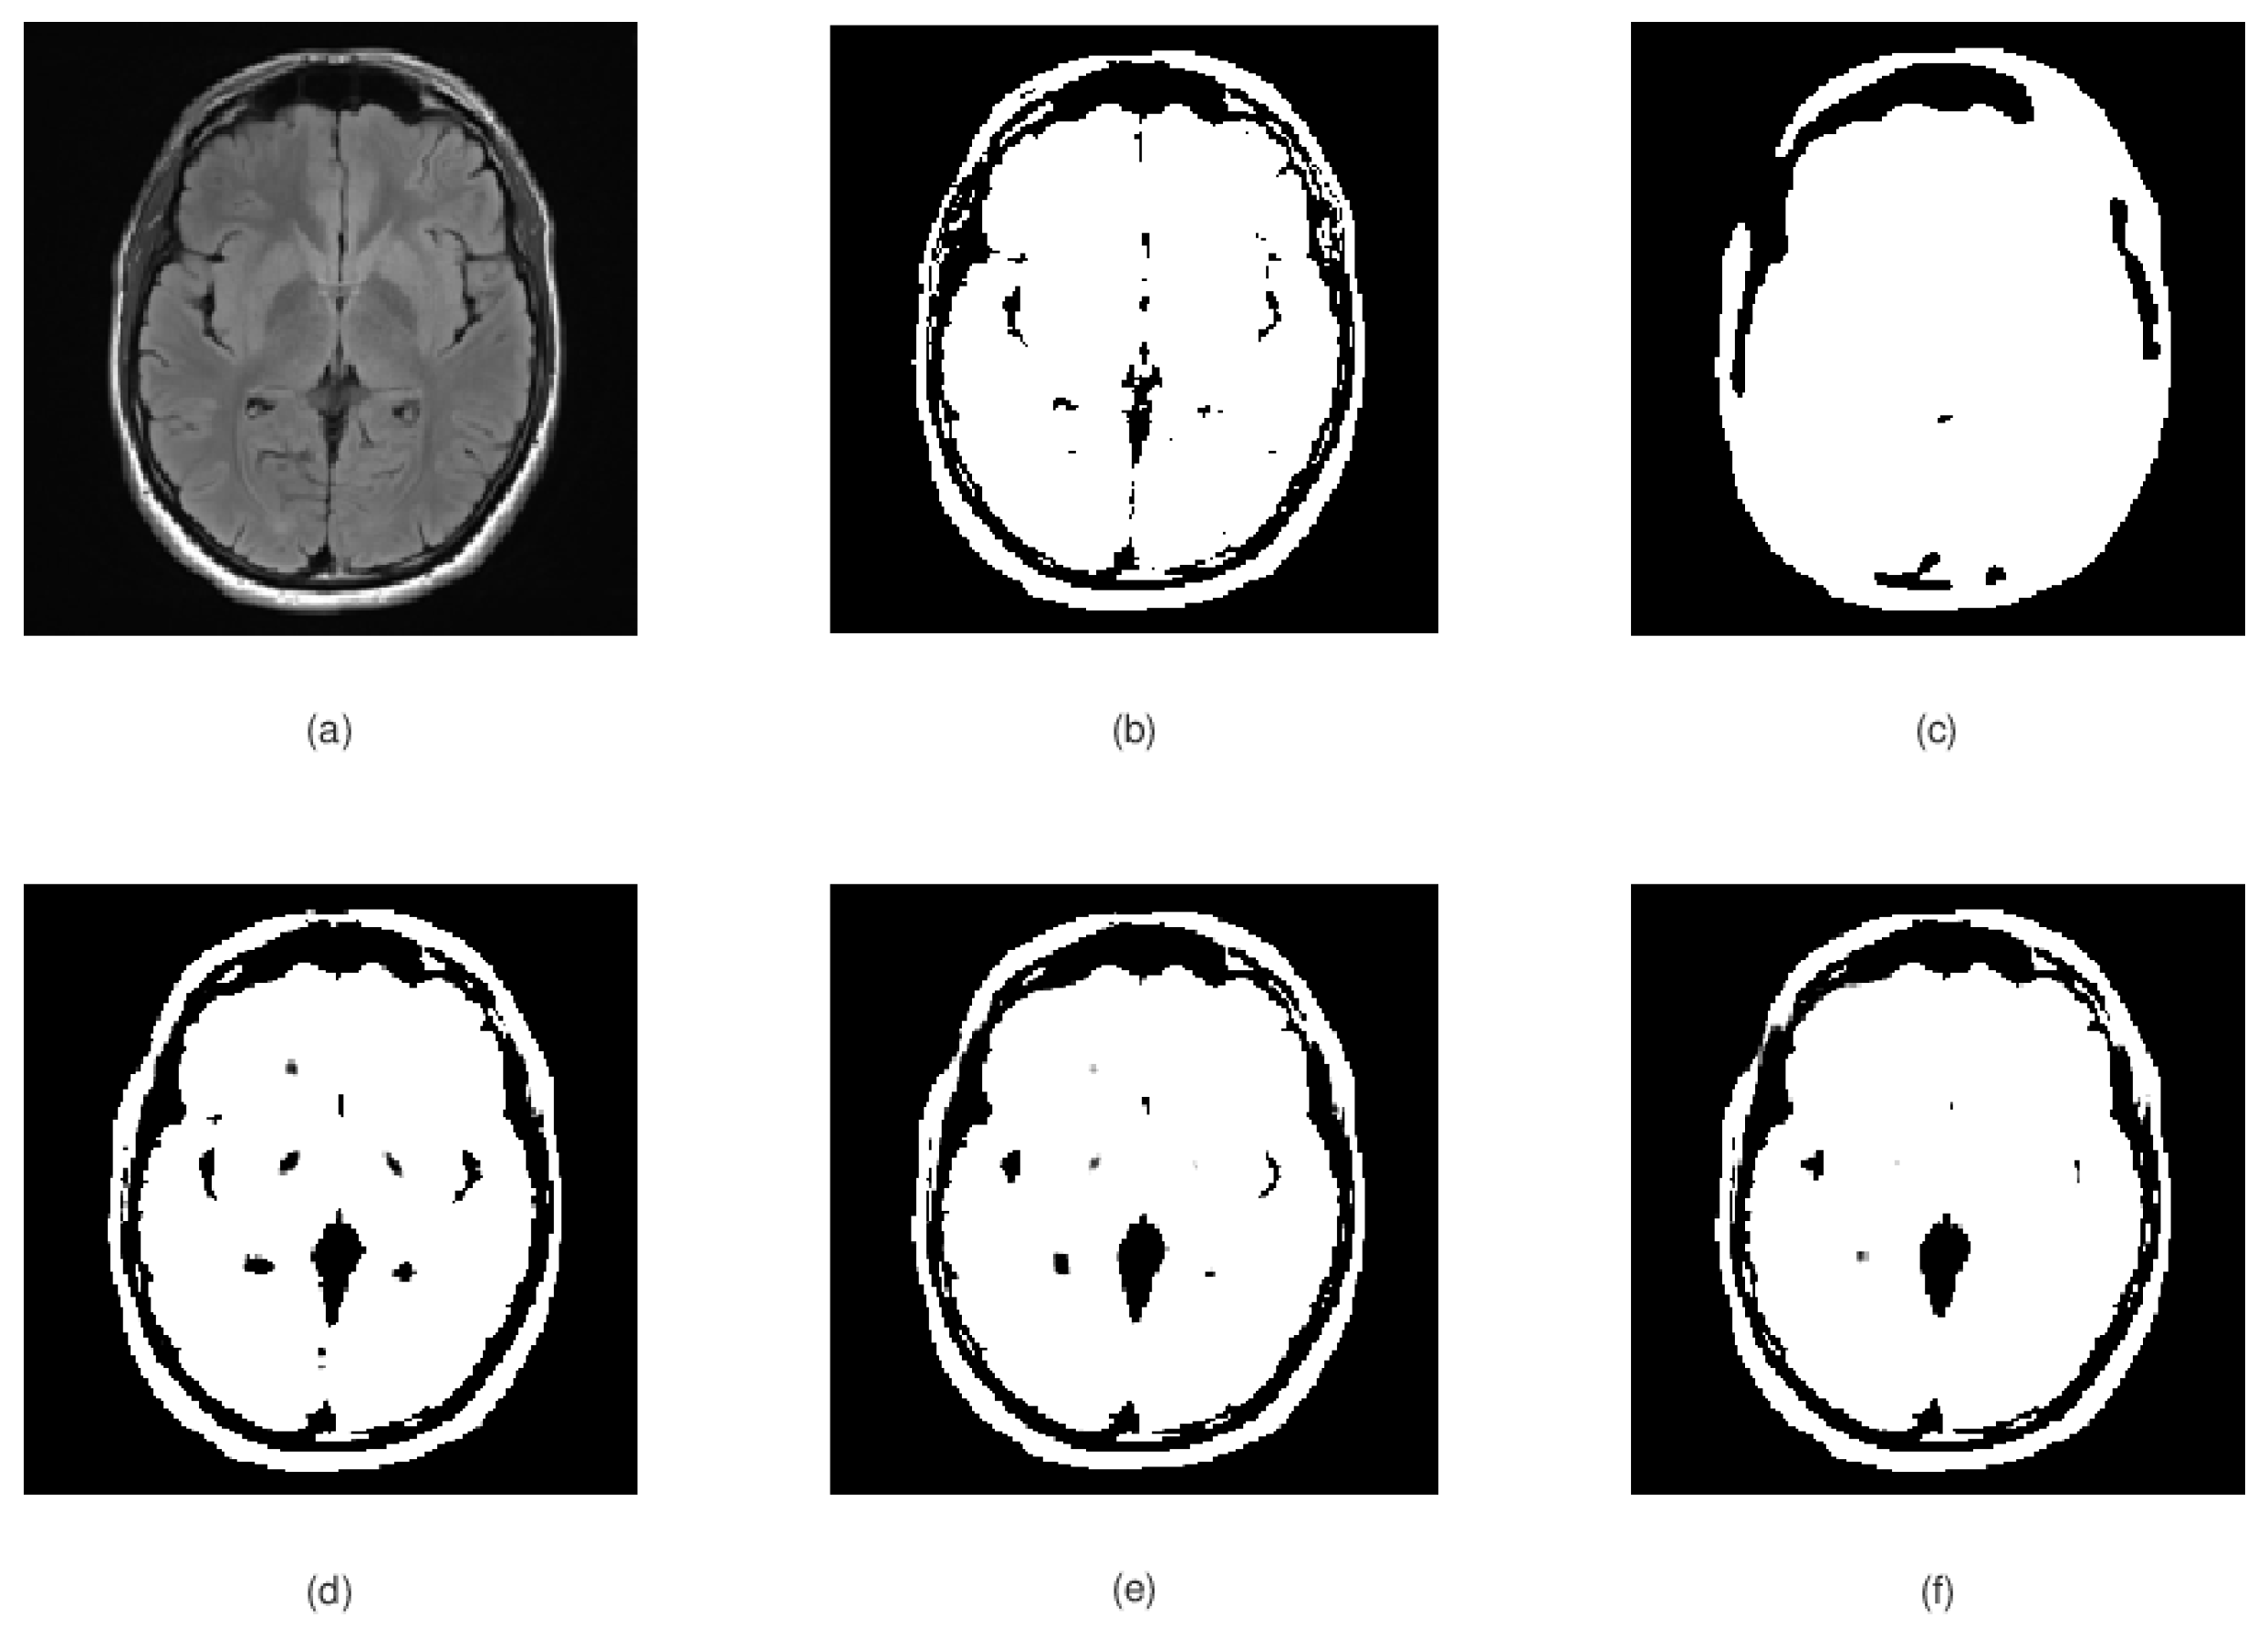

3.2. Experimental Results

- Two two numerical schemes (47) and (48) are constructed to approximate the solution of the mathematical models (31) and (32) (local and nonlocal case).